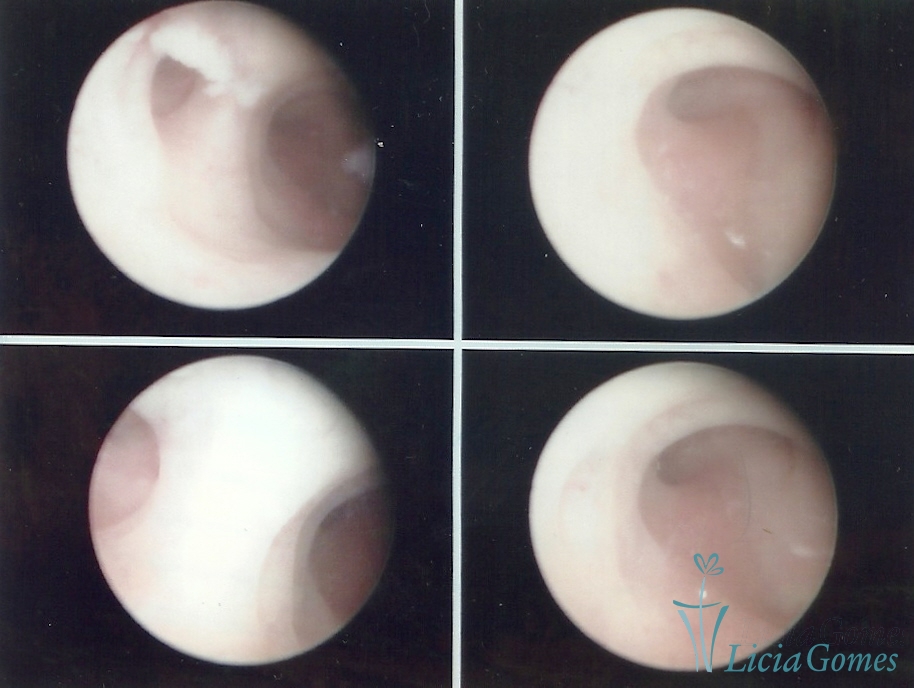

SINÉQUIA TIPO MUCOSA